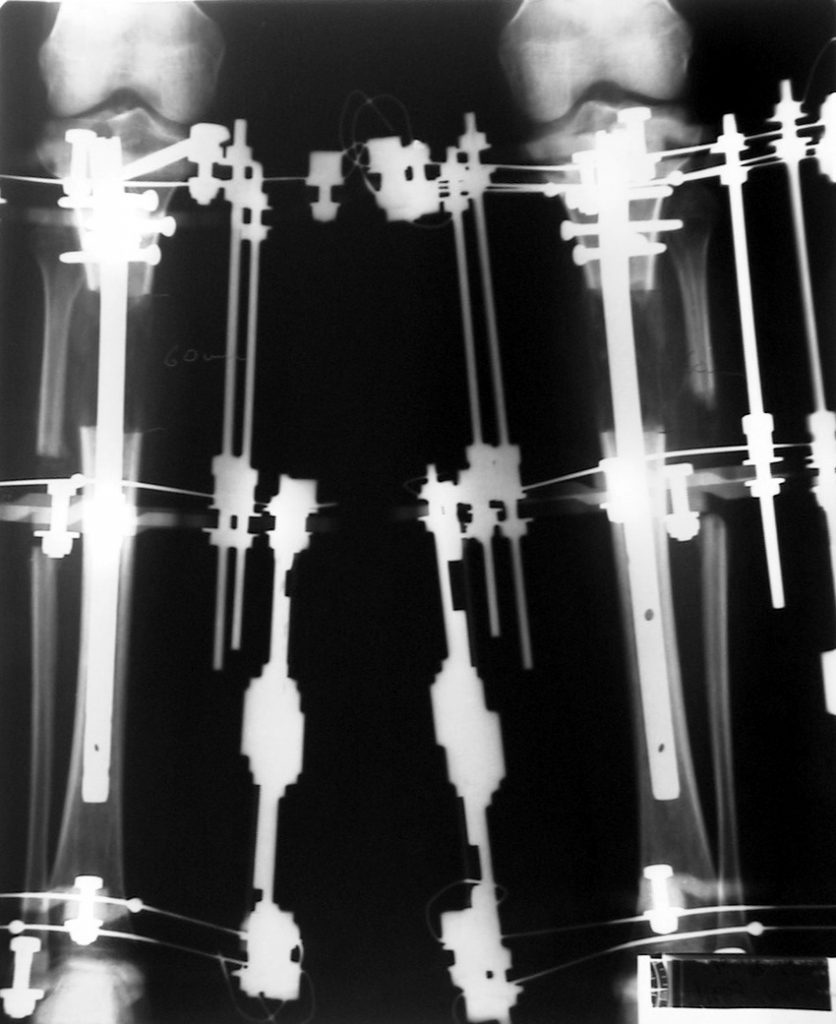

İntramedüller çivinin yerleştirilmesi ve osteotomi: Hasta traksiyon masasına supin pozisyonda yatırılır ve sağlam bacak altta olacak şekilde bacaklar makas pozisyonuna alınır. Standart yolla piriformis çukurundan medulla içine girilir ve kılavuz tel üzerinden kullanılacak çividen 1.5 mm daha kalın oyucu ile medulla oyulur. Proksimal femur, çivinin proksimali daha kalın olduğu için daha kalın oyulur. Radyografide osteotomi hattı planlaması yapılır. Planlama yapılırken uzatma sonunda distalde en az 8 cm. çivi kalması stabilizasyon için gereklidir. Kortikotomi perkütan olarak kortikotom ile tamamlanır. Daha sonra kılavuz tel çivinin boyunu ölçmek için distale ilerletilir. Uygun boyda intramedüller çivi çakılır. Son olarak çivi proksimalden kilitlenir ve bir adet dren konarak ameliyatın birinci kısmı tamamlanır.

Eksternal fiksatör uygulanımı: İntramedüller çiviye değmeden aşağıya ve yukarıya üçer adet Schanz vidası gönderilir. Vidalarla çivi arasında en az 1 mm den fazla mesafe olmalıdır.

Postoperatif Bakım: Distraksiyona (Kemik parçalarının arasının birbirinden uzaklaştırılması yöntemi) 10. günde başlanır. Günde 4 defa 6 saatte bir 0.25mm uzatma yapılır. Operasyondan 1-2 gün sonra kalça ve diz çevresi hareketlere başlanır. Alt ekstremite kısalıklarının tedavisi uzun yıllar boyunca hem hasta hem de cerrah için zorluklarla dolu olmuştur. İlizarov’un distraksiyon osteogenezisi kavramını tanımlamasından sonra geliştirilen teknikler bu konuda yeni bir çağın öncüleri olmuşlar ve daha önceki yıllarda görülen komplikasyonların oldukça azaldığı uygulamalar olarak anılmışlardır.

Biz son zamanlarda, seçilmiş vakalarda, uzatma sonrası uzunluğu ve “alignment’ı” korumak amacı ile unilateral dinamik aksiyel fiksatör ve kilitli intramedüller çivi kombinasyonunu tercih etmekteyiz. Bu yöntemin ön şartları medullanın en dar çapının 7 mm.’den geniş olması ve uzatma sonrası distalde en az 8 cm. uzunluğunda çivi kalabilmesidir. İntramedüller çivi hem uzatma esnasında femurun üzerine gelen makaslama ve bükülme kuvvetlerini nötralize etmekte hem eksternal fiksasyon süresini kısaltmakta, hem de yeni oluşan kemiği kırıklara karşı korumaktadır. Serimizde bir vakada subtrokanterik femoral osteotomi yapılmıştır. İntramedüller çiviye rağmen varus angulasyonu oluşması yönünde bir dezavantaj tespit etmedik.